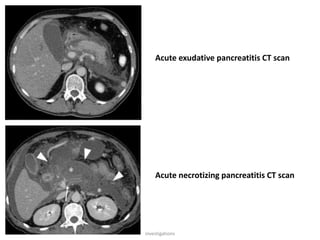

CT scan

• Useful in detecting large pancreas, pseudocyst,

abscess, hemorrhagic pancreas

• Presence of gas bubbles indicate abscess

Acute exudative pancreatitis CT scan

Acute necrotizing pancreatitis CT scan

Plain x-ray abdomen •It may show gall stones, sentinel loop, colon cut off sign, features of paralytic ileus, left pleural effusion or collapsing of lung CT scan • Useful in detecting large pancreas, pseudocyst, abscess, hemorrhagic pancreas • Presence of gas bubbles indicate abscess Ultrasound • To detect gallstone and biliary obstruction and serial assessment of pseudocysts, although in the earlier stages the gland may not be grossly swollen and may be missed on US. investigations

Acute exudative pancreatitisCT scan Acute necrotizing pancreatitis CT scan investigations